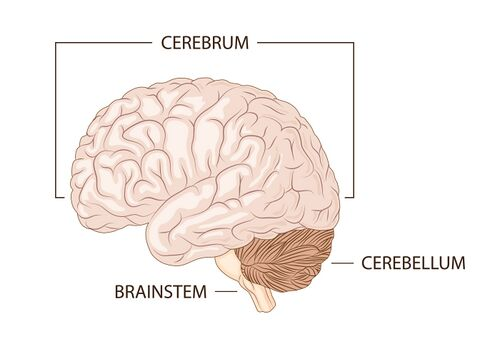

What are cerebrum higher brain functions?

sensory, consciousness,motor control

Brainstem

Which brain region is responsible for coordination of movement (balance)?

Cerebellum